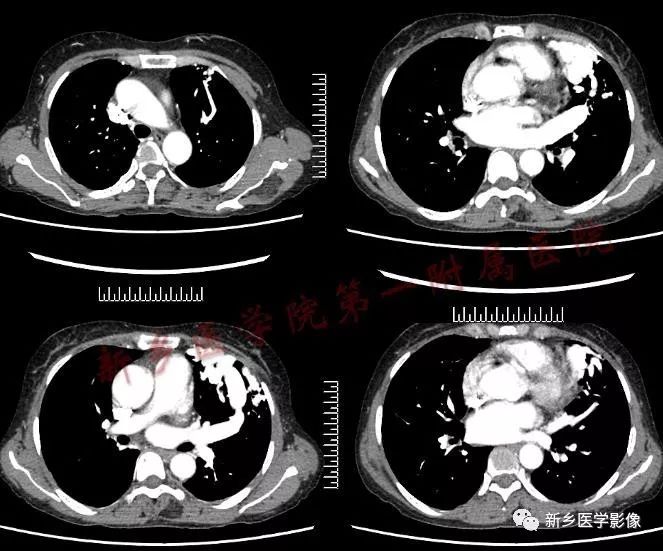

影像学表现

1.结节型 直径<3cm,边缘清晰,密度均匀 2.团块型 直径3-8cm,可有分叶,密度均匀或不均匀 3.弥漫型 肺野散在多个病灶,呈逗点状影,诊断相对较困难 肺动脉造影是诊断金标准,但为有创性。 CT平扫:肺部单发、多发结节或囊袋状影 CTA:①血管蒂征,扩张的血管囊边缘有供血动脉及引流静脉 ②动脉瘤、供血动脉与胸部供血大血管强化一致,引流肺静脉及左心房提前显影。 国外CT表现分型: 1.可分辨解剖结构型 引入动脉及引流静脉 2.结节型 密度均匀结节状影,CT增强病灶直径增大1cm,并与大血管同步强化可确诊。 3.管状型 分隔或不分隔的弓状影 鉴别诊断 1.炎性假瘤:多有炎性病史,边缘呈“方形征”或“刀切征”,增强扫描呈均匀强化,但强化程度不及PAVM。 2.肺癌:边缘分叶、毛糙,周围有浸润,有阻塞改变,增强强化程度不及邻近大血管 3.结核球:边缘光滑或有长毛刺,其内密度较低,可见钙化灶,周围可见卫星灶。增强扫描不强化或边缘强化。 4.肺内富血供结节病灶:主要由支气管动脉供血,时间密度曲线应与左心室与主动脉强化时间一致,且肺内富血供实质结节病灶多为恶性病变,边缘不光整,可见毛刺、分叶 5.肺静脉曲张:为肺静脉局限性扩张,临床很少有症状。一般认为是肺静脉壁先天性缺陷或肺静脉高压造成。病灶靠近左心房,CT扫描两下肺内圆形、椭圆形或管状明显强化,强化程度与左心房一致,无PAVM特征性的供血动脉和引流静脉。